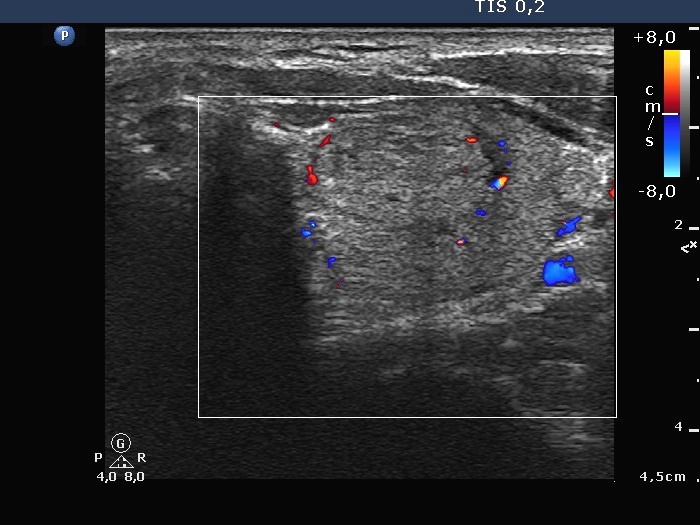

Right lobe, horizontal view

Middle part of the left lobe, horizontal view. This lesions presents signs of perinodular blood flow, as well.